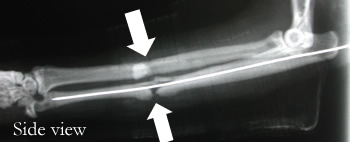

I spent almost all of Friday in the O.R. and I had a blast! (Not commonly said after a day in the OR.) I saw two full surgeries. As always, I can only share minimal detail because of patient privacy laws. The first was a hardware removal. The surgeon removed three 7-9″ screws from a knee that had been broken during a sports practice. The second was a forearm fracture. This one really showed me that surgery is not a delicate process, like you see on TV, at all. To fix this fracture the doctor hammered a long metal rod up the radius. Insert into bone, hammer ten times as hard as possible, x-ray, repeat until rod is fully up arm. I cringed the whole time.